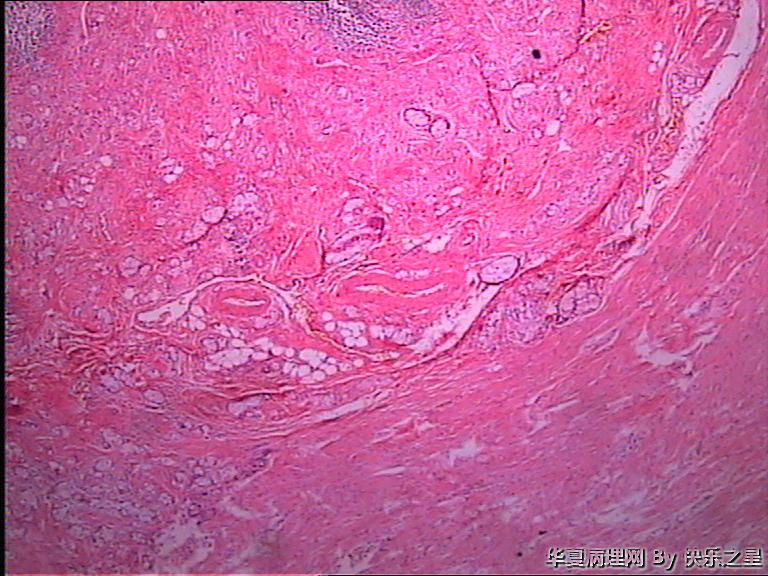

阑尾杯状细胞腺类癌?

男,73岁,因回肠坏死手术,术中切除部分回肠及回盲部,附带 阑尾,长6.5,粗0.7-1.2,表面水中、充血,管腔闭塞,成实性,切面灰白、暗红,质中。

能想到杯状细胞类癌就很不错了!是不是类癌或腺类癌就得看免疫组化了。不怕做不到,就怕想不到。

首选转移性阑尾杯状细胞类癌鉴别印戒细胞癌

应该是类癌,正常腺体不会在肌层内浸润。